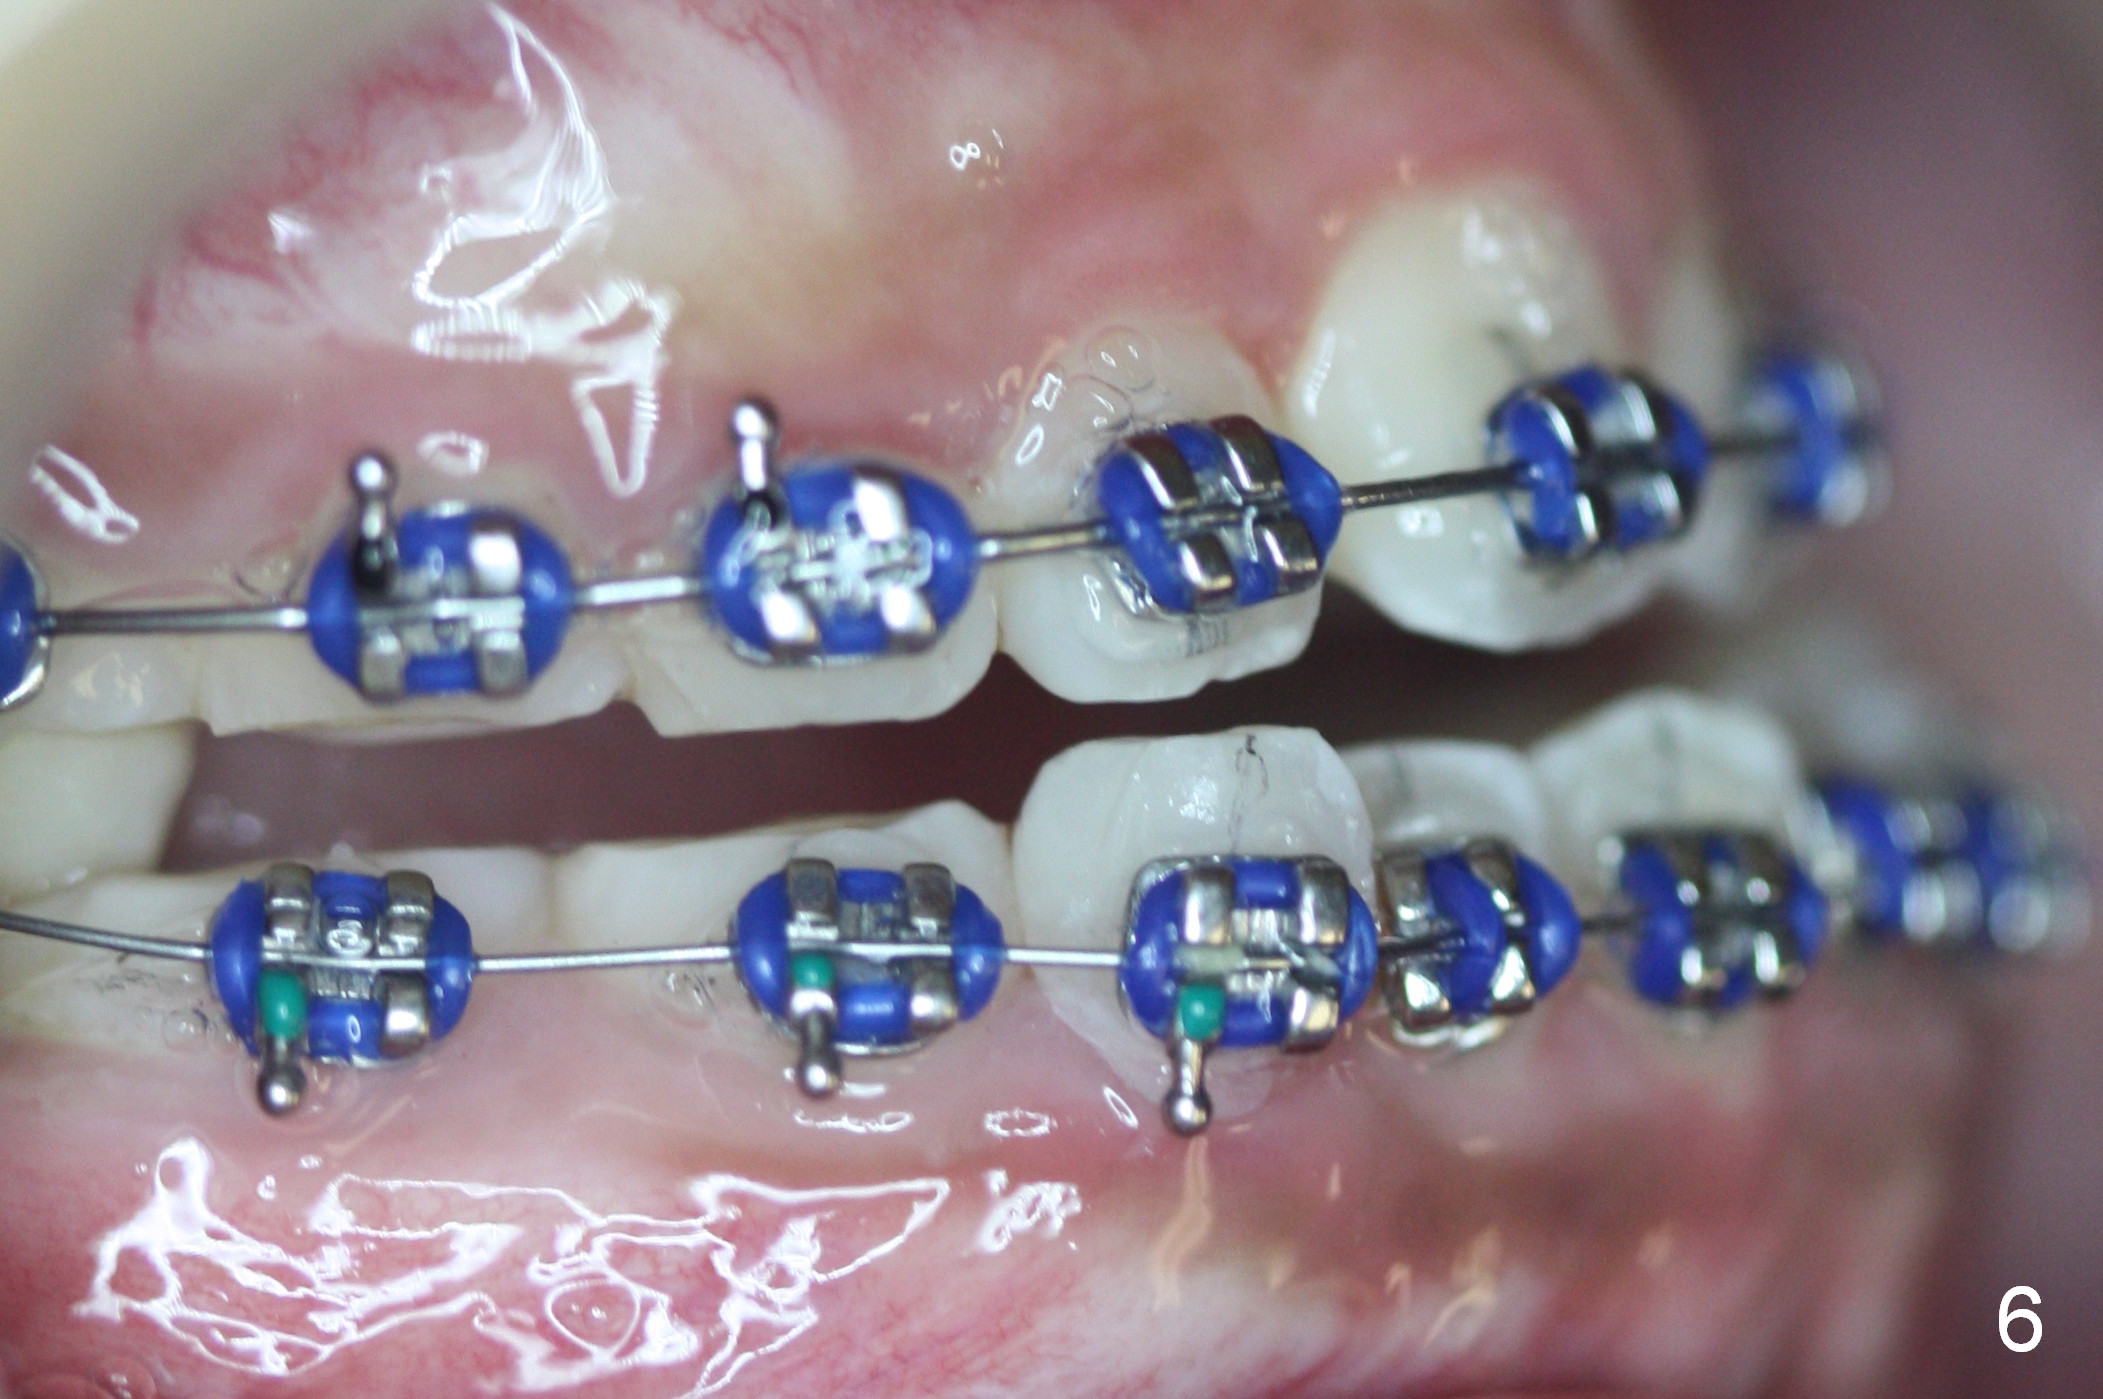

The 2nd visit post bracketing, the lower brackets are placed (Fig.5). The cross bite is still not completely fixed (Fig.6).